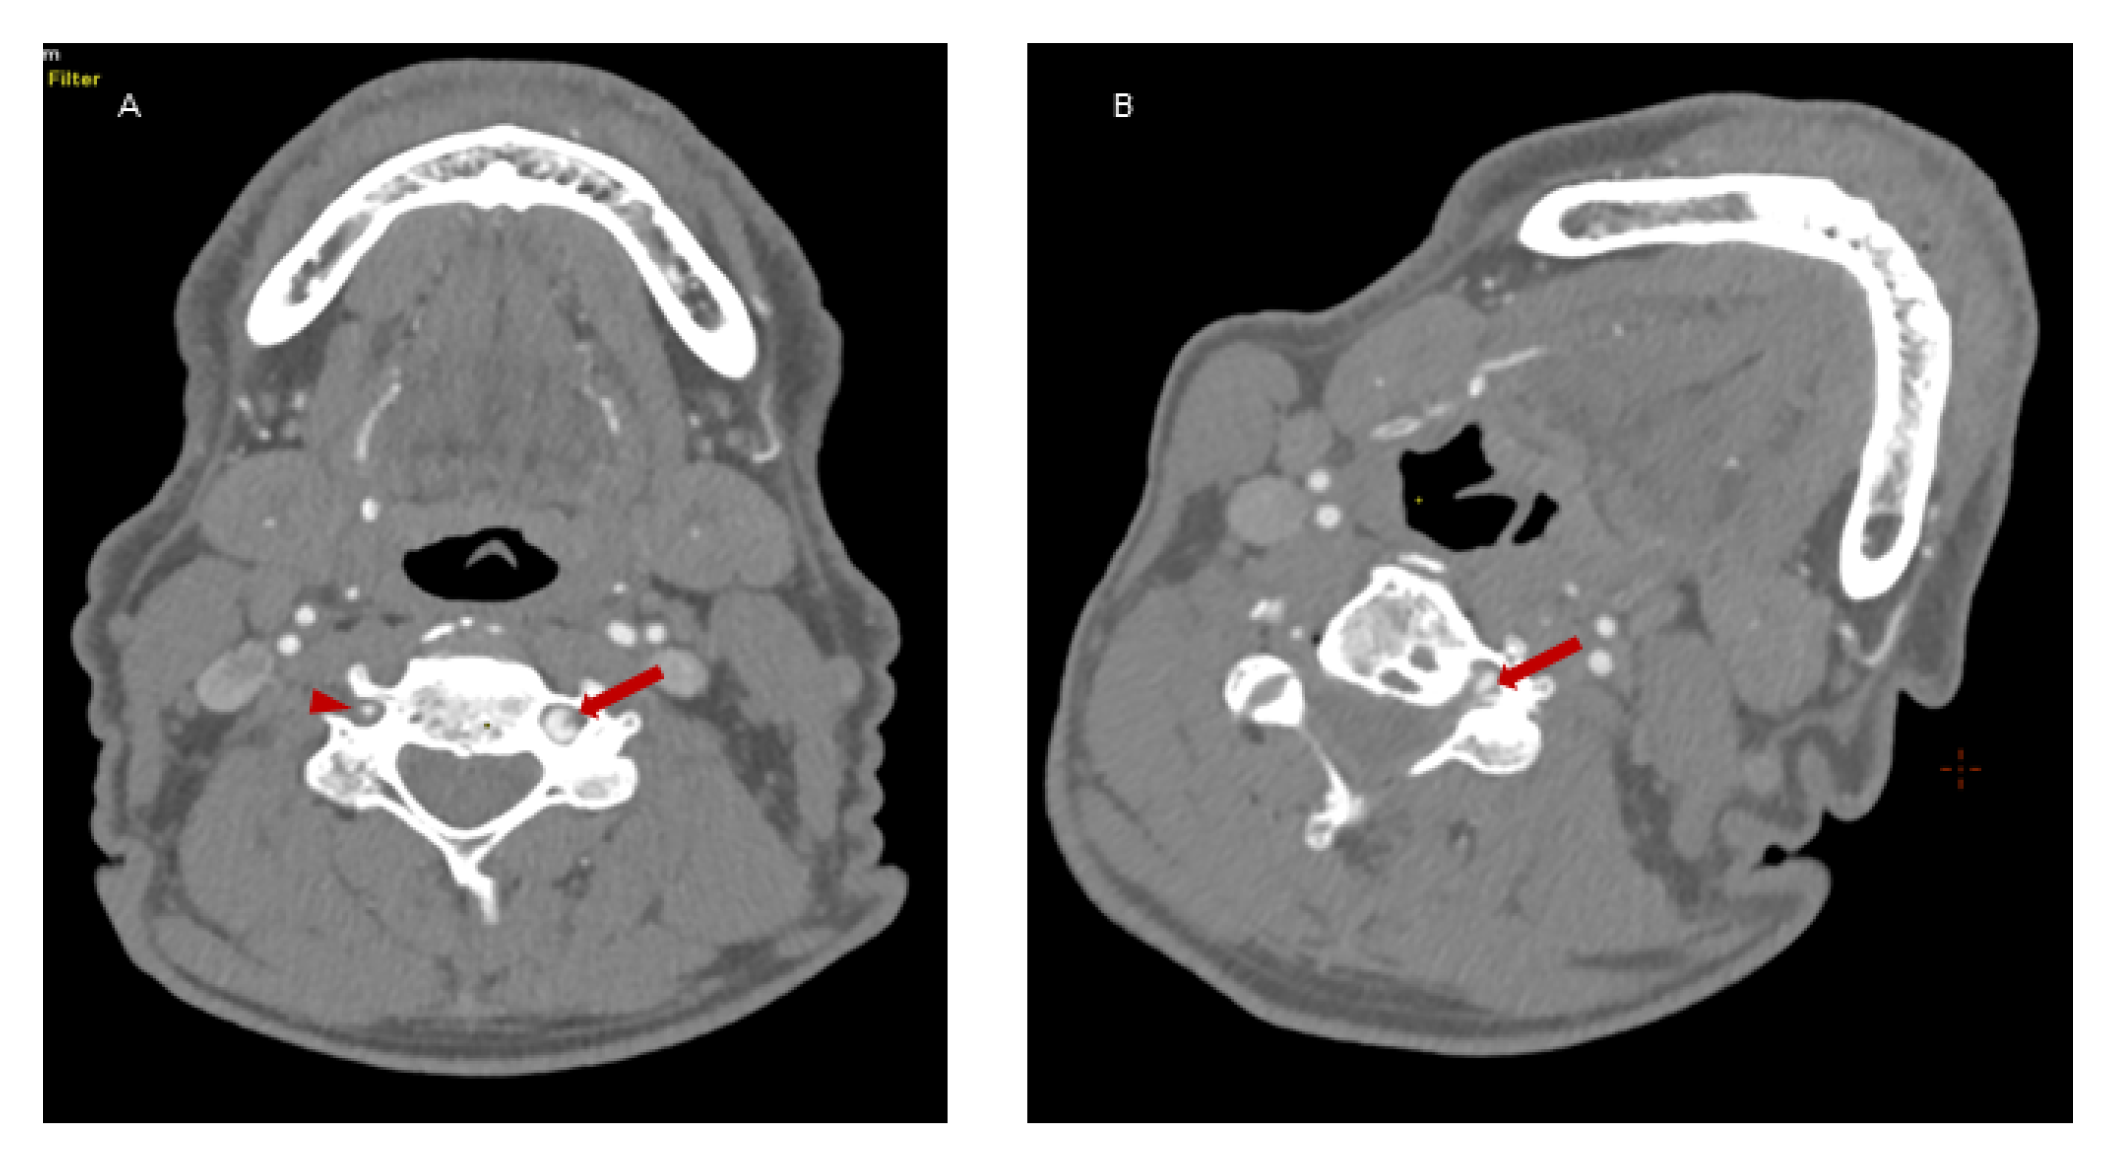

Because of the suspected dynamic stenosis, a dynamic CT angiography (D-CTA) of the carotid, vertebral and cerebral arteries was performed. Firstly, the imaging was conducted with the patient’s head in the neutral position. It revealed atheromatous plaques in both carotid bulbs (slightly calcified; maximum thickness: 2.8 mm) with no hemodynamically significant stenosis, grade 2 of kinking of R-ICA and a tortuosity of L-ICA. Furthermore, hypoplasia of R-VA was demonstrated (widths: R-VA 1.9 mm; L-VA 3.6 mm). L-VA had a tortuous course and it formed a loop at the level of the C4 vertebrae. There was no L-VA stenosis in this position (Figure 2A). Subsequently, D-CTA was acquired during left-side rotation of the head. In this examination the lumen of L-VA was narrowed up to 2 × 3.2 mm, causing 60% stenosis according to the NASCET criteria (Figure 2B) [7]. 3D reconstructions of this pathology were also obtained (Figure 3A,B). It was also observed that basilar artery (BA) was formed exclusively by L-VA. No abnormalities of other cerebral arteries were observed.

Figure 2. Dynamic CT angiography in the neutral head position and left-side rotation. Panel (A): Axial D-CTA in the neutral head position demonstrates L-VA loop in V2 segment (red arrow) at C4 level and R-VA hypoplasia (red arrowhead). No L-VA stenosis in this position. Panel (B): Axial D-CTA in left-side head rotation demonstrates the narrowing of L-VA lumen (up to 2 mm × 3.2 mm) that causes a dynamic 60% L-VA stenosis in the loop at C4 level (red arrow).